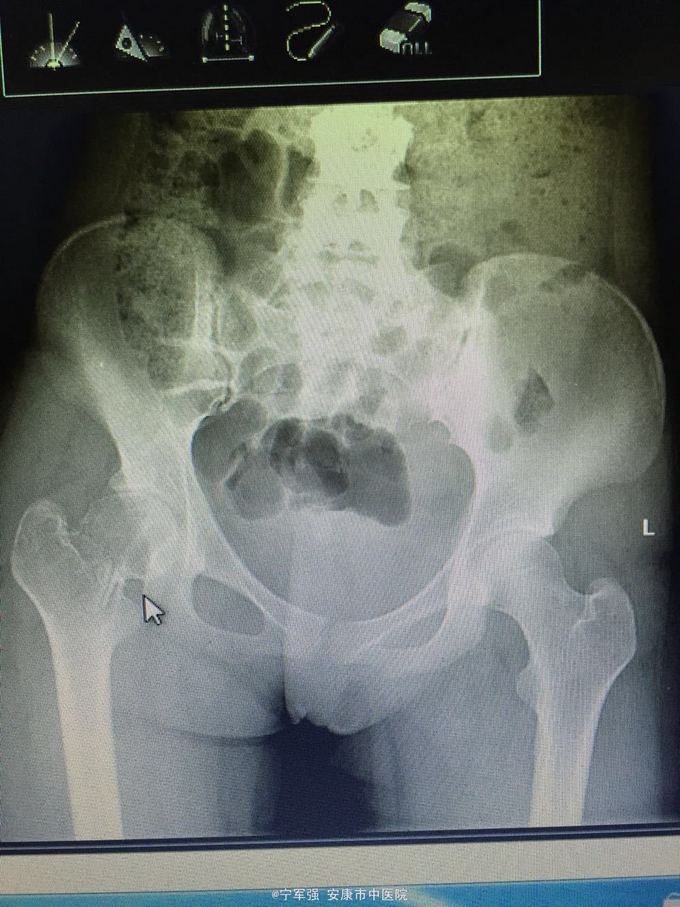

女性,20岁,外伤后右髋部疼痛不适活动受限 伤前身体尚可,5个月前有右大腿不适感,当时未行X线检查

查体:右髋部稍肿,局部压痛(+),纵向叩击痛阳性,右下肢短缩约1.5CM,末梢血运及皮肤感觉良好。 肿瘤标志物(-),碱性磷酸酶不高。

右股骨颈病理性骨折 处理:1.进一步完善检查髋关节MRI。 2.病检,确定性质; 3.消肿对症治疗; 4.择期植骨内固定术